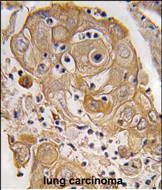

- Formalin-fixed and paraffin-embedded human lung carcinoma tissue reacted with PTRF antibody (N-term) (Cat.#P33864), which was peroxidase-conjugated to the secondary antibody, followed by DAB staining. This data demonstrates the use of this antibody for immunohistochemistry; clinical relevance has not been evaluated.